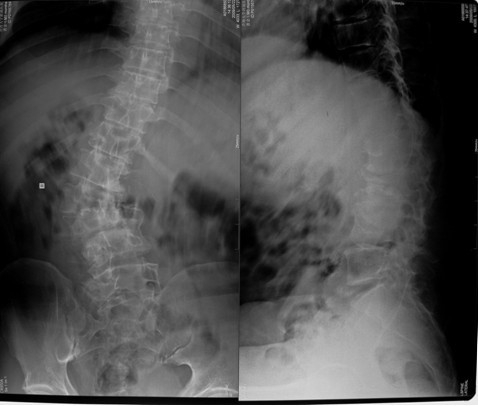

本组46例中男28 例,女18 例。年龄17~67岁,病程6 个月~7年,平均11.3 个月。本组患者均为 L1~S1腰段结核。病灶累及2 个椎体31例(L1-2 6例, L2-3 8例,L3-4 10例,L4-5 5例,L5-S1 2例),3 个或3 个以上椎体15例。合并腰大肌脓肿23列,所有患者均有腰背部疼痛,活动受限,双下肢感觉麻木19例,会阴部感觉减退12例,双下肢肌力减弱12例,腱反射减弱12例,术前后凸角(Cobb 角) <30°者12例, 30°~60°者28 例, >60°者6 例,Cobb角平均32.3°4例患者是二次手术。术前均行X线片、CT或者MRI检查。术后病理检查确诊为脊柱结核。

本组手术用时间3~4h , 平均3.5h 。术中出血300~500ml , 平均约350ml 。术后症状完全缓解,无神经功能障碍加重等并发症,1例营养差的老年患者伤口出现窦道,1例因肝功能差,术后未口服抗痨药,伤口出现窦道,经换药后二期愈合,其余病例伤口均一期愈合。马尾神经受损的患者术后基本恢复正常。术后一周后凸角平均 5.4°后凸畸形平均矫正90%以上, 最终后凸角平均8.3°,后凸角度平均丢失4.2°。随访3个月有87%(40/46)有骨痂形成,6个月91.3%(42/46)明显骨性愈合(见图),其余4例9-12个月内愈合,随访时间3-32个月,平均11个月,46例患者中2例在术后2个月和3个月时背部形成脓肿,换药后治愈。2例出院1月后并发结核性脑膜炎,治疗后好转。1例因椎弓根钉偏外,刺激神经根,5个月后从侧方脱出,疼痛加重,因前后路植骨完全愈合,取出后症状完全缓解。